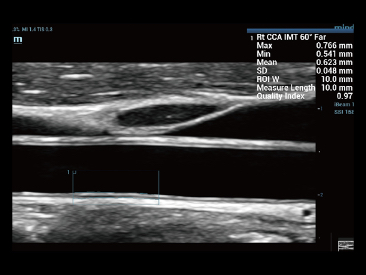

Sinds de oprichting van het bedrijf is Mindray voortdurend op zoek naar nieuwe manieren om het diagnostisch vertrouwen te vergroten. Resona 7 wordt aangestuurd door de meest revolutionaire ZONE Sonography?-technologie. Zijn nieuwe ZST+-tilt de kwaliteit van ultrasoundbeeldvorming naar een hoger niveau door middel van zoneacquisitie en kanaalgegevensverwerking.

Naast de hoogwaardige beeldvormingskwaliteit verbetert de Resona 7 tevens de klinische onderzoeksmogelijkheden met de revolutionaire V Flow voor vasculaire hemodynamische evaluatie, en de intelligentste vlakacquisitie van een 3D-gegevenssets voor de diagnose van het foetale, centrale zenuwstelsel. Met zijn combinatie van de meest intu?tieve, op vingerbewegingen gebaseerde multi-aanrakingsbediening en alle essenti?le klinische functies loopt de Resona 7 voorop in de nieuwe golven van ultrasoundinnovatie.